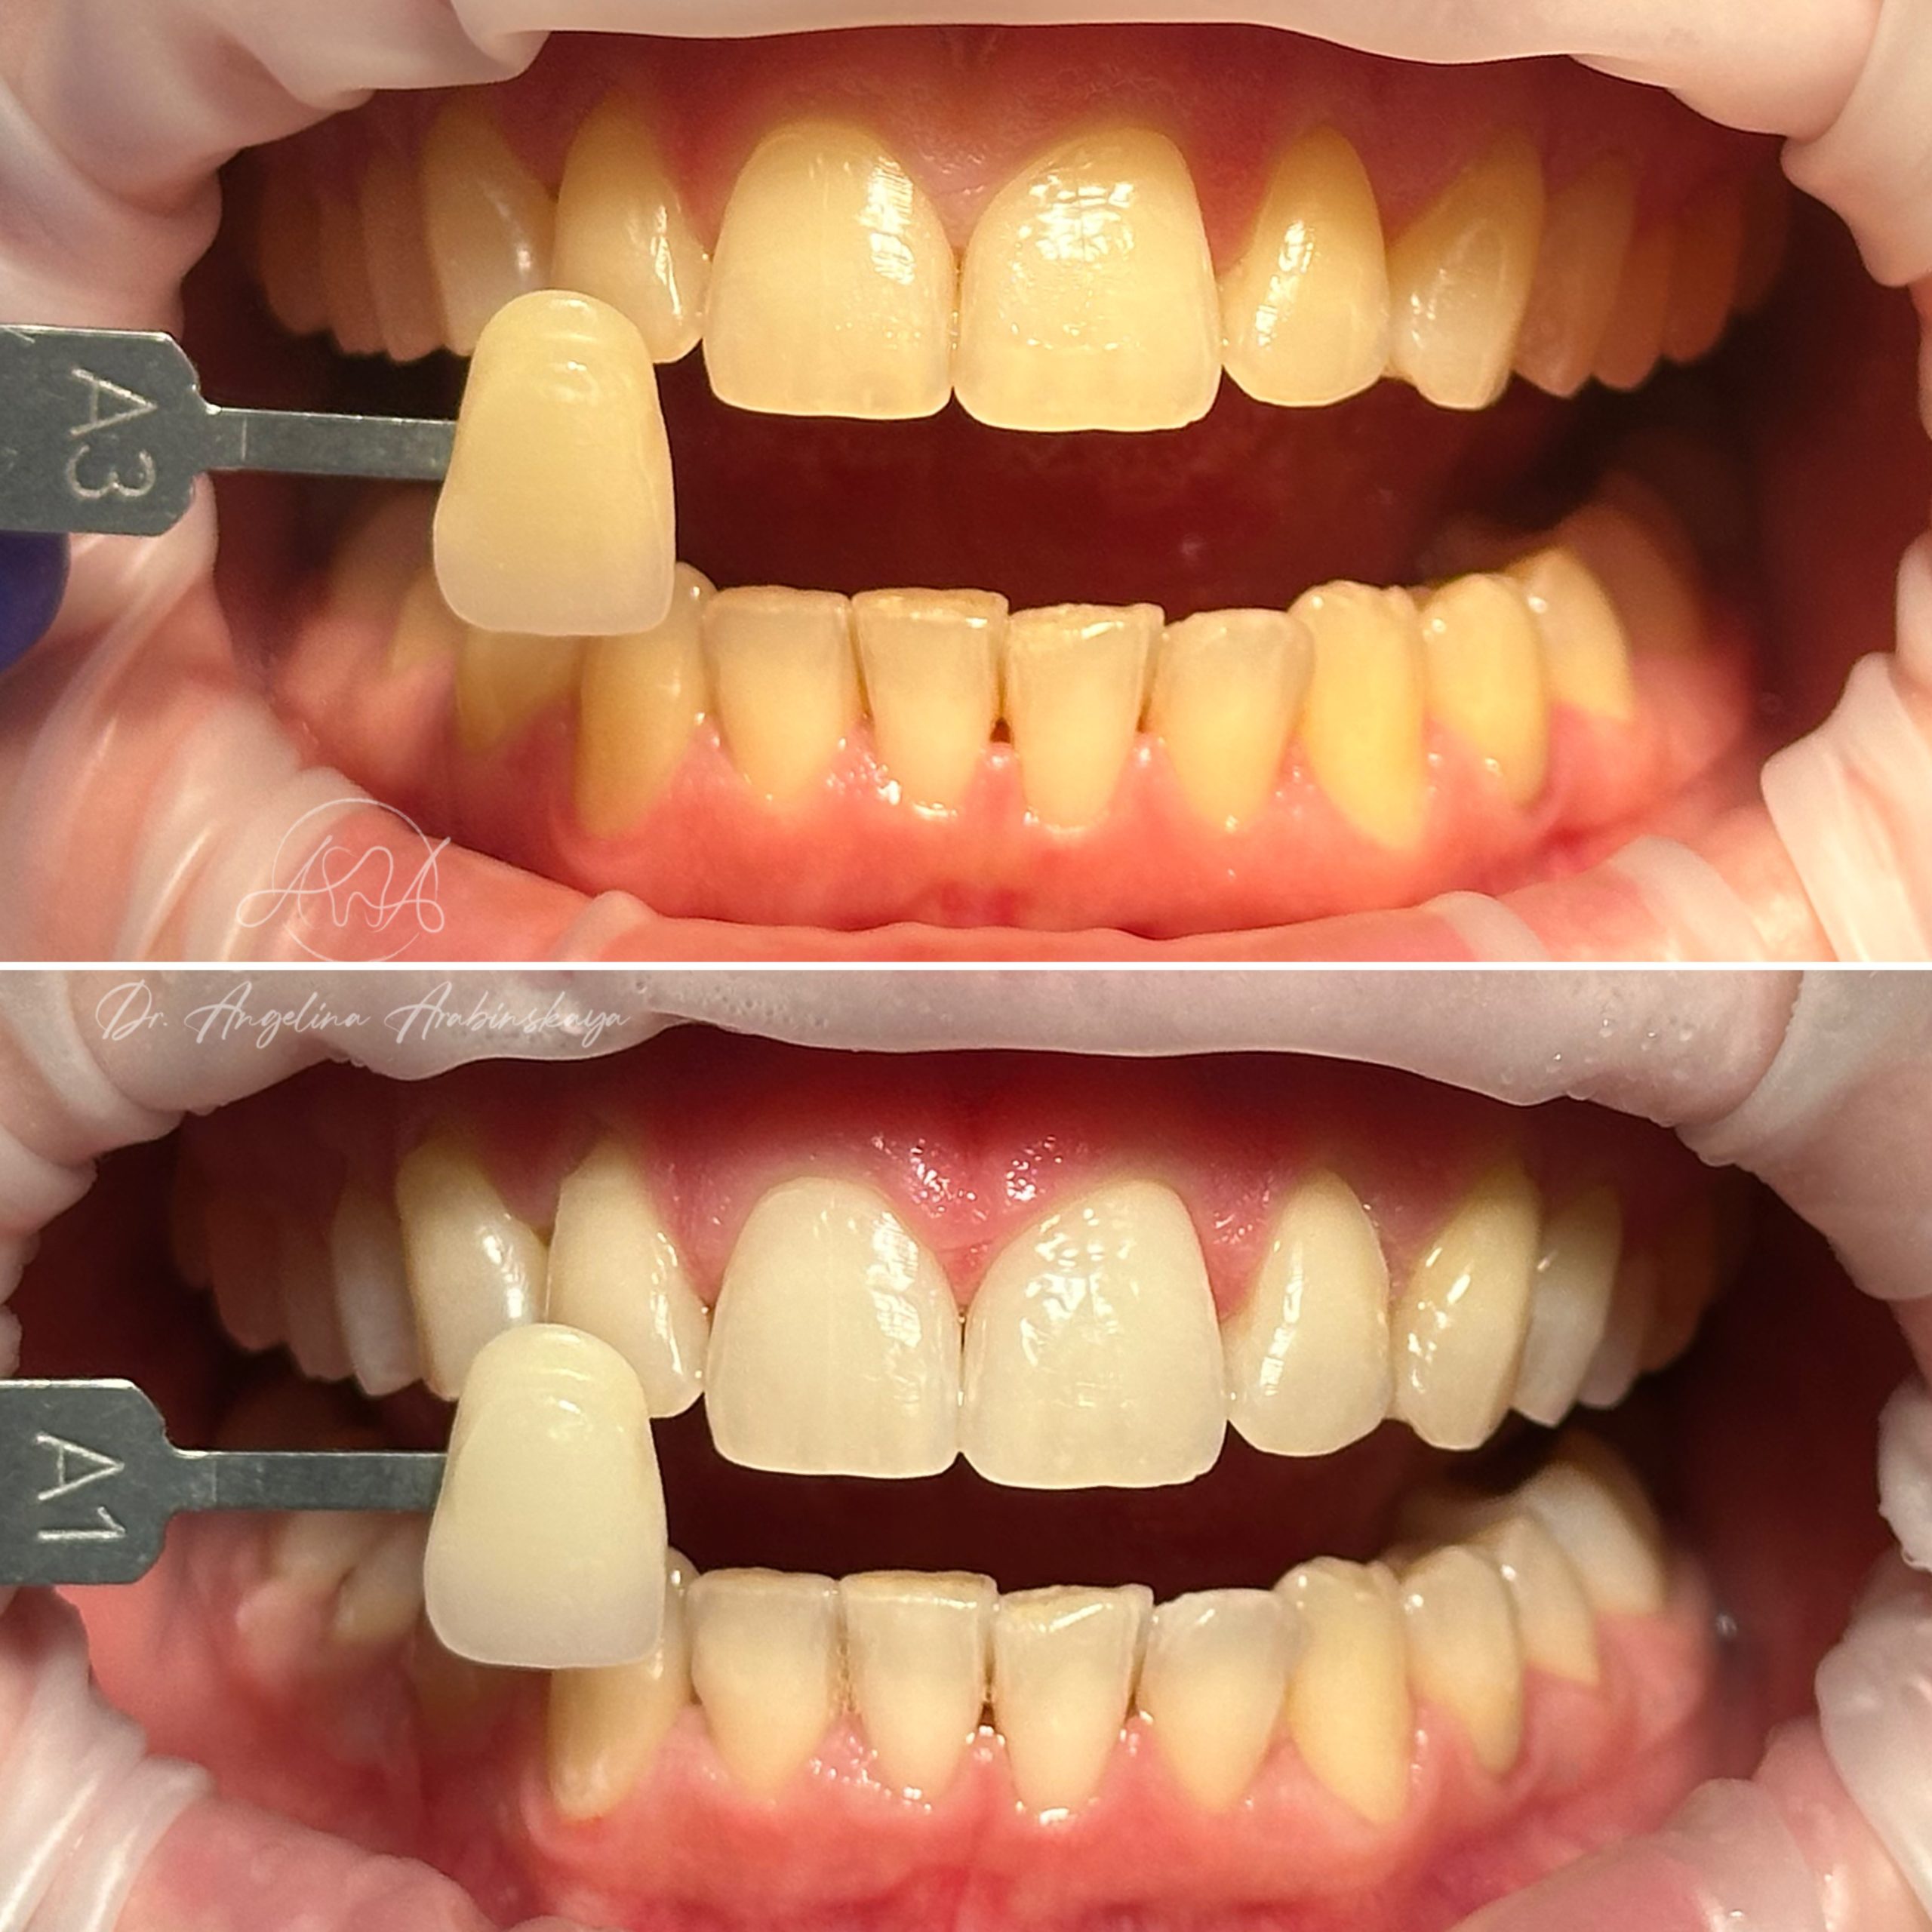

• Профессиональная отбелка зубов системой ZOOM,BEYOND

• Домашнее отбеливание зубов

2024 год – «Отбеливание от «А» до «Я» Александр Кирманов